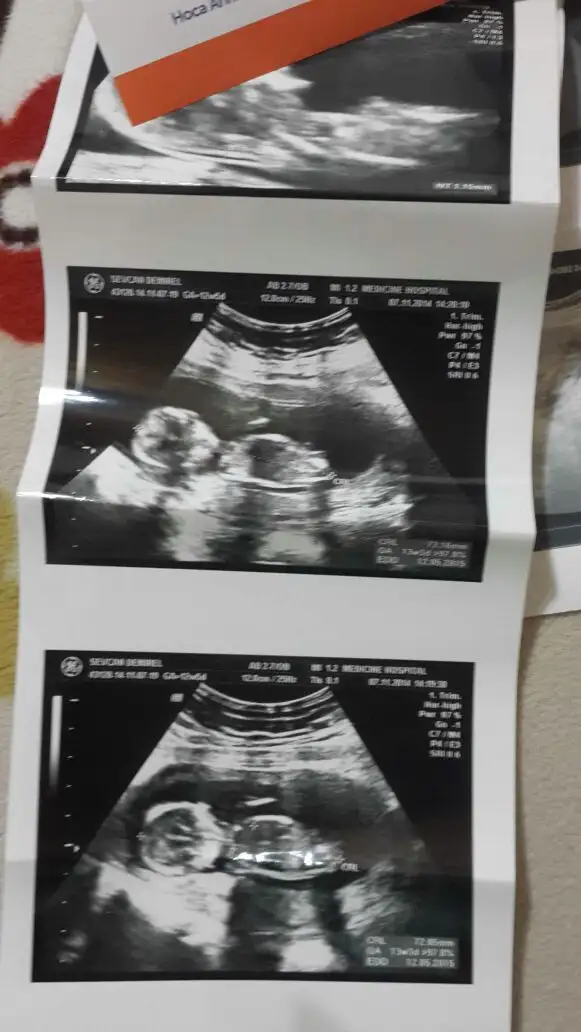

Kızlar benimkinide tahmin edin lutfen cok merak ediyorum 13 haftalığım

Zeyyal ve mavi ikinizinkinide kiza benzettim öğrenince haber verin

Net gorebiliyo musun ? Haftaya gittigimde cekilen fotoyu da atiyim mi canim ?kiz goruyorum hep ruyamda. Genelde ters cikar ruyalarim ama bu kez duz cikti sanirim. Allahim saglikla dogmasini nasip etsin

[QUOTE="zeyyal, post: 37794764, member: gördüğümisNet gorebiliyo musun ? Haftaya gittigimde cekilen fotoyu da atiyim mi canim ?kiz goruyorum hep ruyamda. Genelde ters cikar ruyalarim ama bu kez duz cikti sanirim. Allahim saglikla dogmasini nasip etsin[/QUOTE]

Net diyemem canm haftaniz 13 ve paralel gordugum bisi var egr o nub ise ve hala paralel duryo oyuzdem kiz olabilivegini düşündüm kesin haber ver tamammi merak ettim bakalim dogrumu gormusum gordgum nubumuymus anlamis olurum